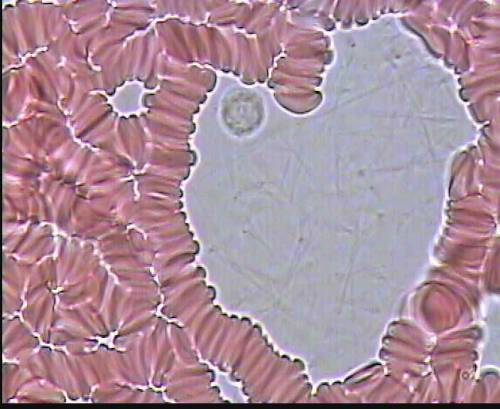

» Кровь при сердечно-сосудистой патологии

Кровь при сердечно-сосудистой патологии